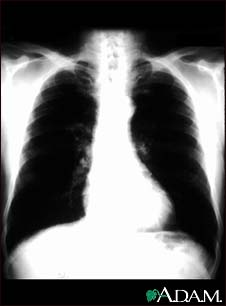

Bronchial cancer - chest X-ray

This is a chest x-ray of a person with bronchial cancer. This is a front view. The lungs are the two dark areas. The heart and other structures are white areas visible in the middle of the chest. The light areas that appear as subtle branches extending from the center into the lungs are cancerous.